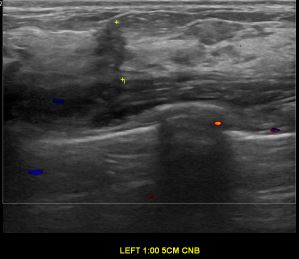

상기환자는 외부 건강검진 이상소견으로  정밀검사위해 내원하신 40대 초반

여성분으로 의심스러운 좌측유방혹 조직검사 시행해 유방암으로 진단되었습니다